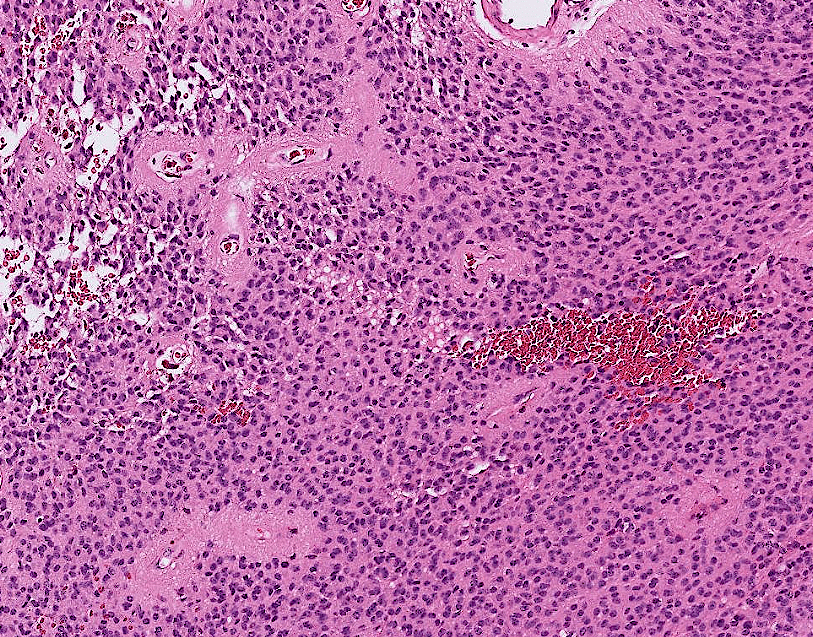

lung adenocarcinoma